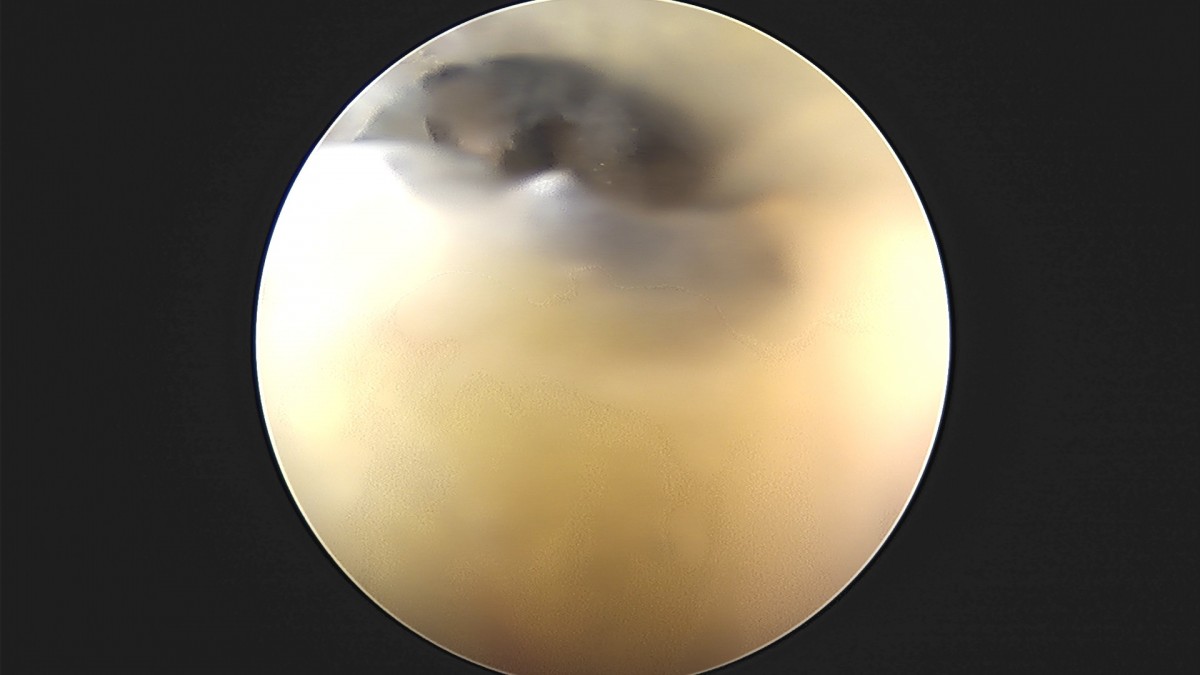

이재상원장님 어깨 견봉하 감압술 및 관절낭 이완술 박창O 환자

dae765e4d9ac96aee867c9d6292d8784_1758004612_2234.jpg